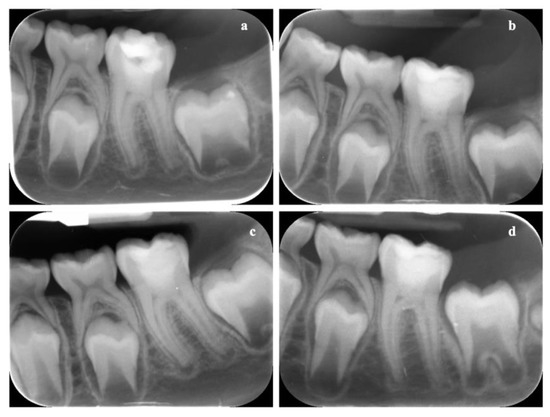

3.8. In Vivo Results